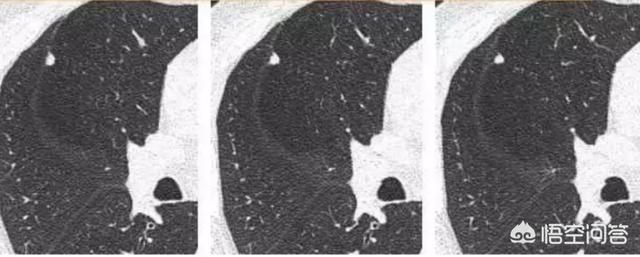

Ein kleiner solider Knoten wie dieser, etwa 4 mm, war glatt und zeigte keine offensichtlichen Anzeichen von Bösartigkeit. Aber zwei Jahre und vier Monate später:

Die Pathologie bestätigte später, dass es sich um einen kleinzelligen Lungenkrebs handelte.